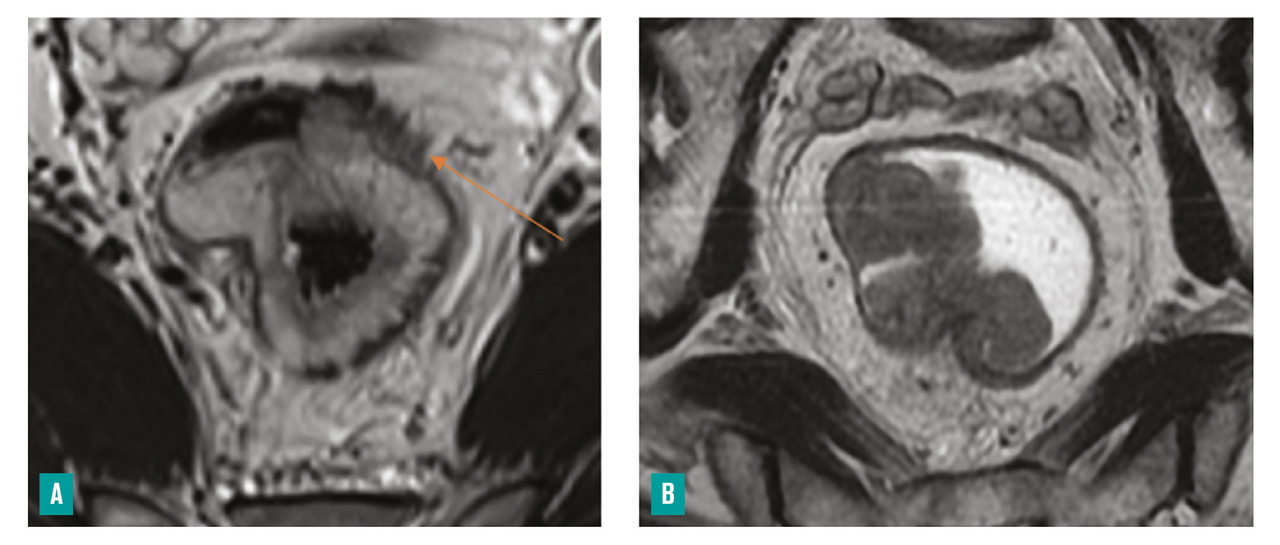

– la présence ou non d’arguments en faveur d’une histologie mucineuse, de plus mauvais pronostic (tumeur en hypersignal T2)4 [fig. 4 ] ;

– la présence ou non d’arguments en faveur d’une histologie mucineuse, de plus mauvais pronostic (tumeur en hypersignal T2)4 [